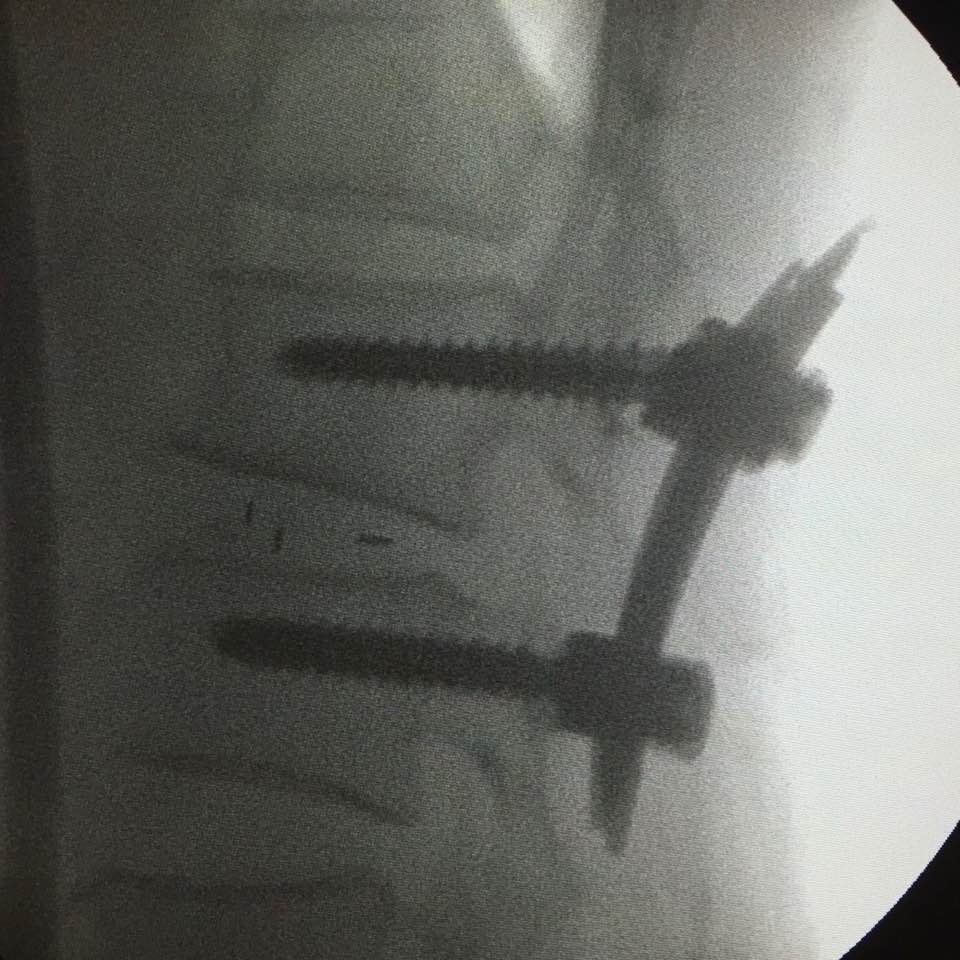

After the operation, he is now happily receiving the help of the lower back screws!